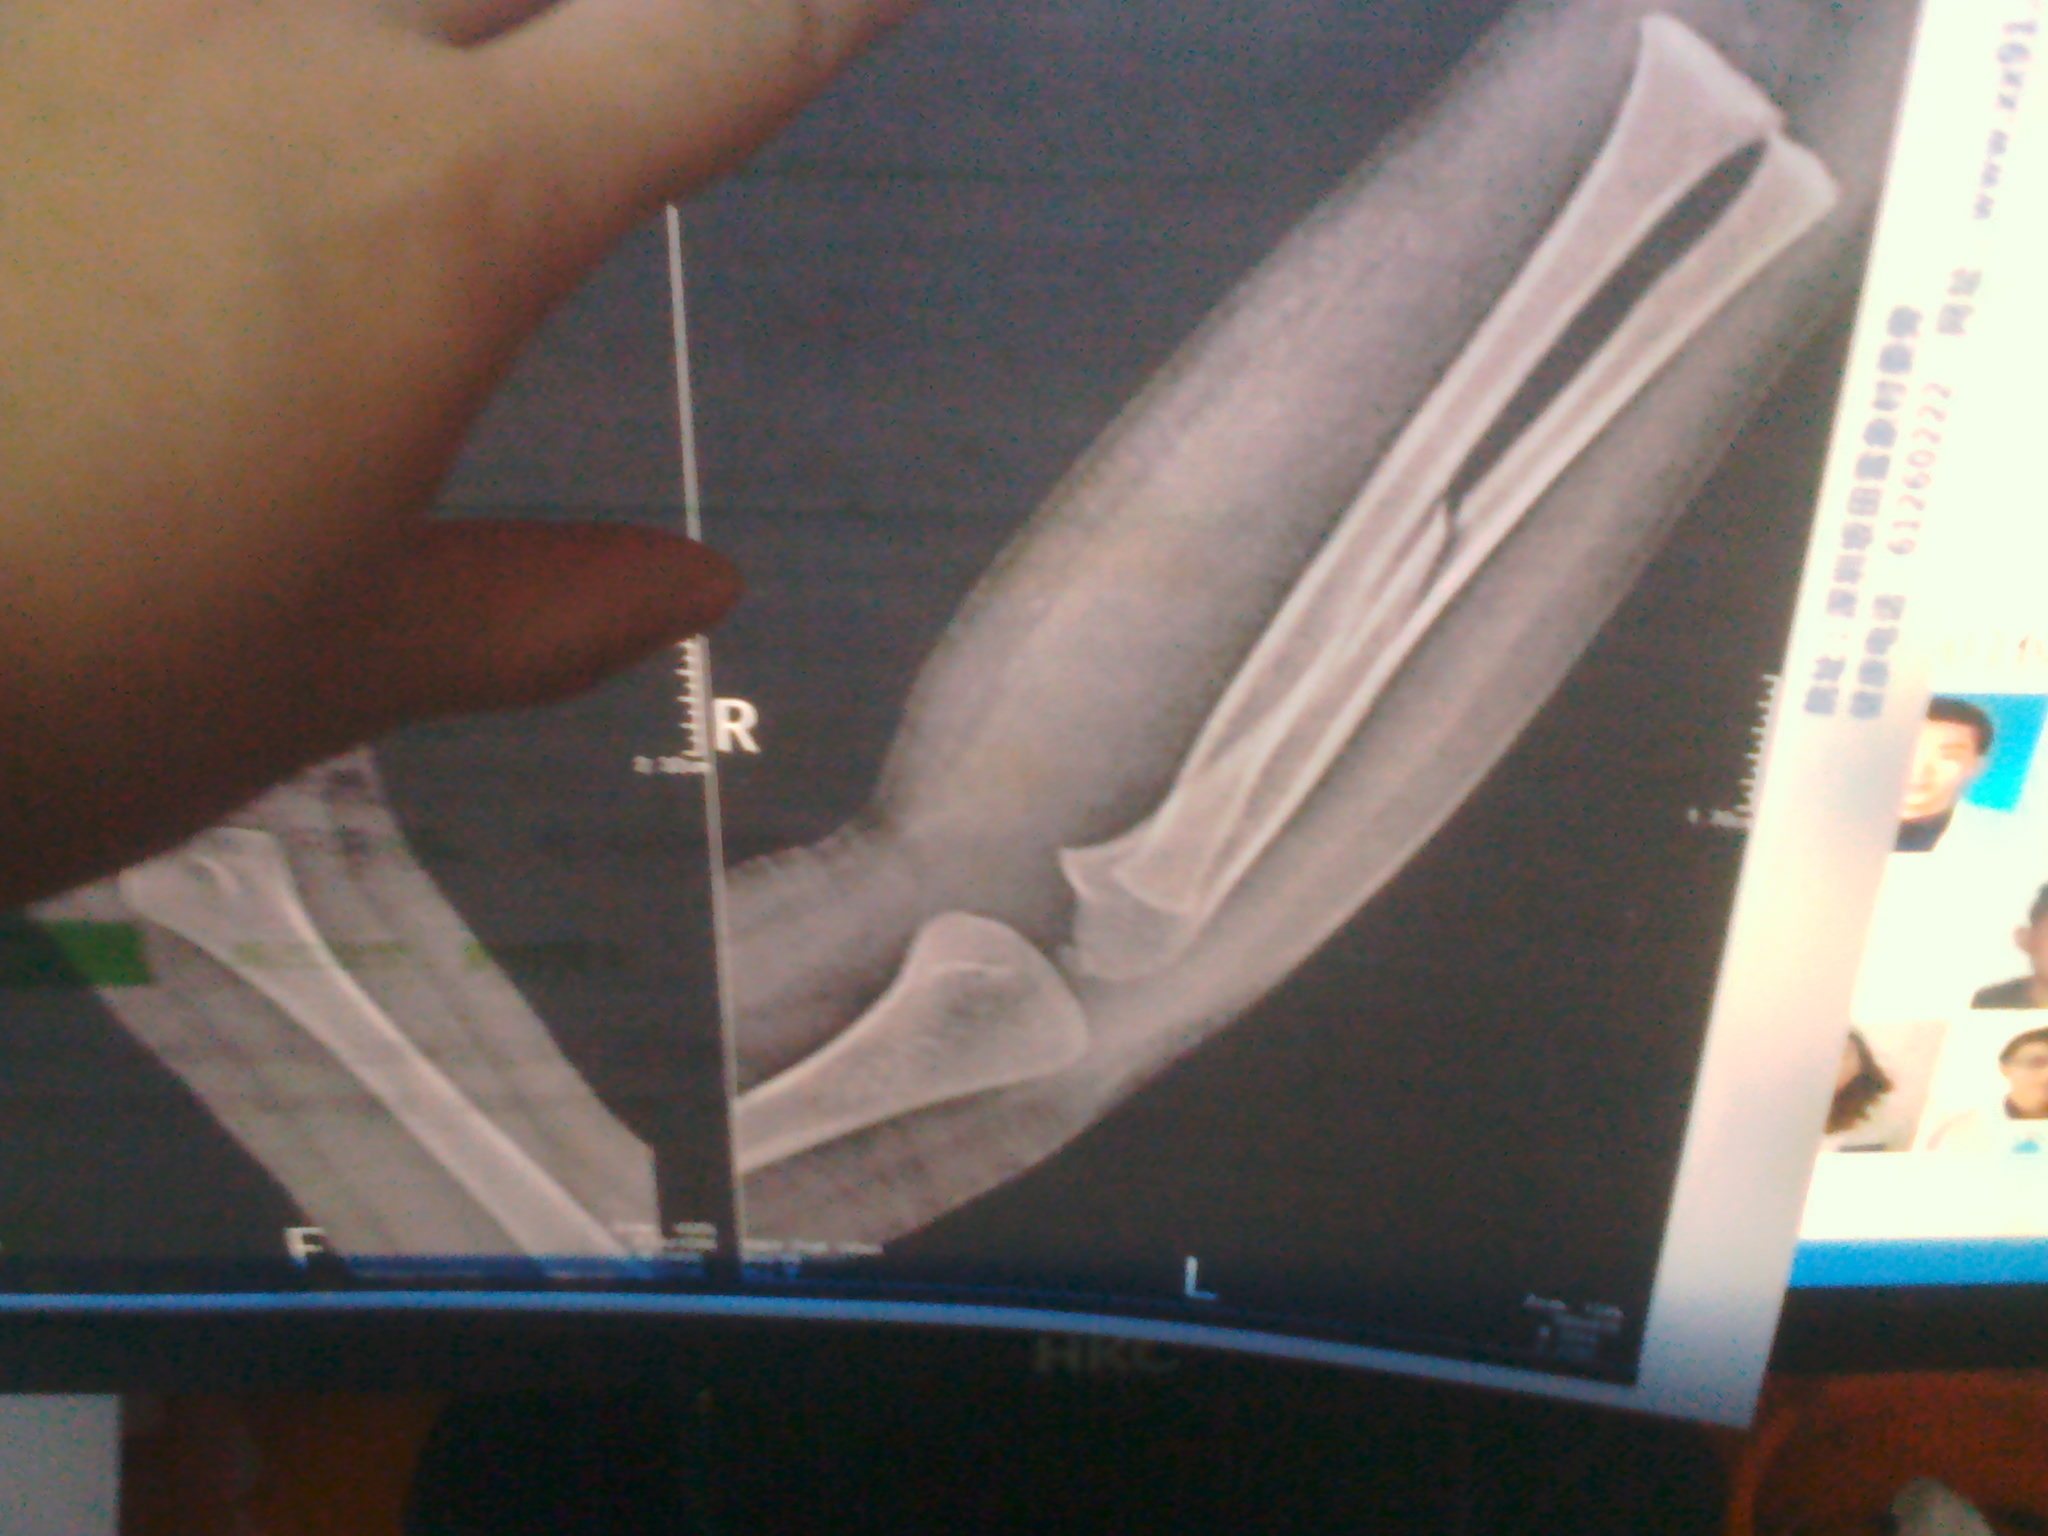

小孩右手的右尺骨中段斜行骨折需要多久才好?打了6天的石膏,什么时间去复查最好,移位的可能性有多大? 点击展开 匿名用户 2014-01-18 19:57 为您推荐: 其他回答 病情分析: 治疗骨折的最终目的是使受伤肢体最大可能的。 指导意见: 最大限度的恢复其功能。因此。在骨折治疗中,其复位、固定、功能锻炼这三项基本原则十分重要 居高洁_uuAP 2014-01-18 20:07 相关问题 后跟粉碎性骨折移位4mm可否只做石膏固定治疗… 七岁儿子在幼儿园摔了跤…右手尺骨骨折…没住院只是打了石膏在家照顾呢…我想问问索赔的话我该怎么办…